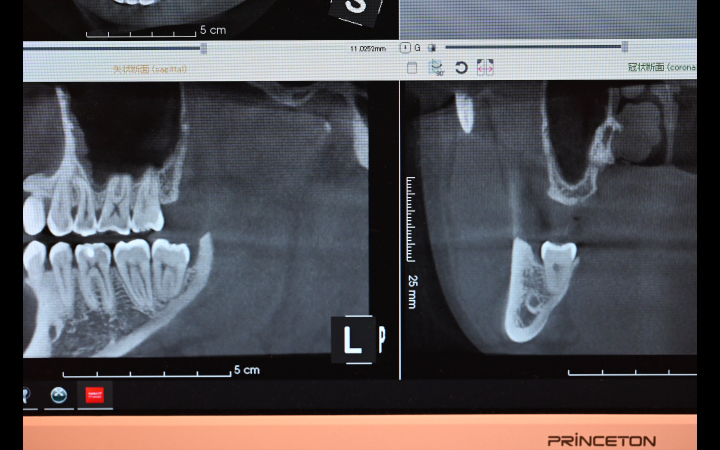

⚫︎CTでの精密診断の必要性

通常のレントゲン(パノラマX線写真)だけでは、親知らずの位置や根の形が二次元的にしか分かりません。特に 下あごの親知らず では、神経や血管が通っている「下顎管」と近いことが多く、抜歯の際に注意が必要です。

歯科用CTを撮影すると、三次元的に確認できるため、次のような点がはっきり分かります。

• 親知らずの根と神経・血管との距離

• 根の形や曲がり方

• 周囲の骨との関係

• 上あごでは上顎洞(副鼻腔)との距離

この情報をもとに、より安全で確実な抜歯計画を立てることができます。